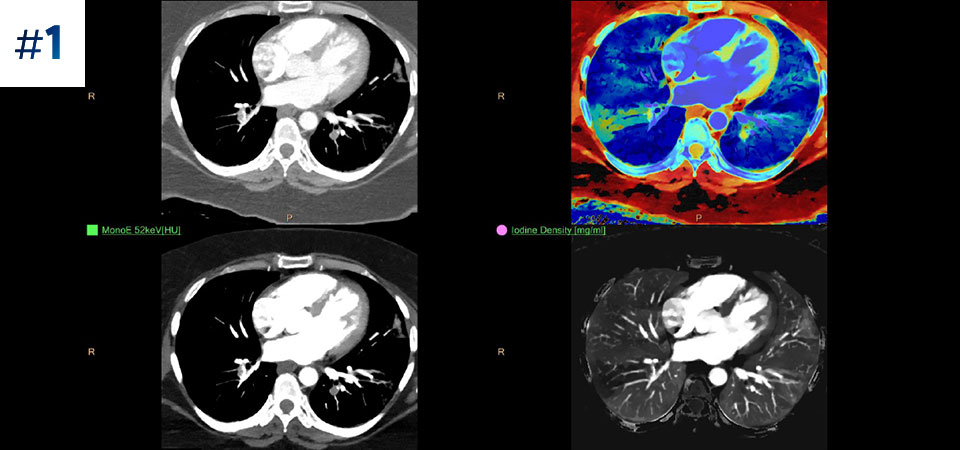

Vá além da CT convencional. Veja de que forma os vários tipos de resultados obtidos com deteção espectral podem aumentar a fiabilidade do seu diagnóstico.

Conheça a diferença entre a CT com detetor espectral e a CT convencional